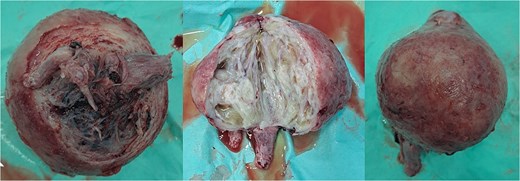

On examination, she was hypertensive and mildly tachycardic. No abdominal mass was identified. Her gynecology evaluation revealed a large pink mass with erosion and white plaque measuring around 30 × 10 × 8 cm (Fig. 1). No cervix-like structure or external uterine ostium was identified, but a point-like structure was identified on the apex, suspected to be the tubal opening. The mass consisted of a cystic and solid part. We suspected that it was a submucosal leiomyoma that had degenerated with cystic parts. Abdominal ultrasound revealed no uterus-like structure and visualized the bladder. The patient was diagnosed with NPUI and submucosal leiomyoma, and a hysterectomy was planned after stabilizing the blood sugar level.

Uterine inversion with submucosal leiomyoma on the corpus. The mass was found to be eroded and covered with slough. A point-like structure was identified at the apex of the mass, suspected of being the tubal ostium; however, the opening of the cervical canal was not identified.